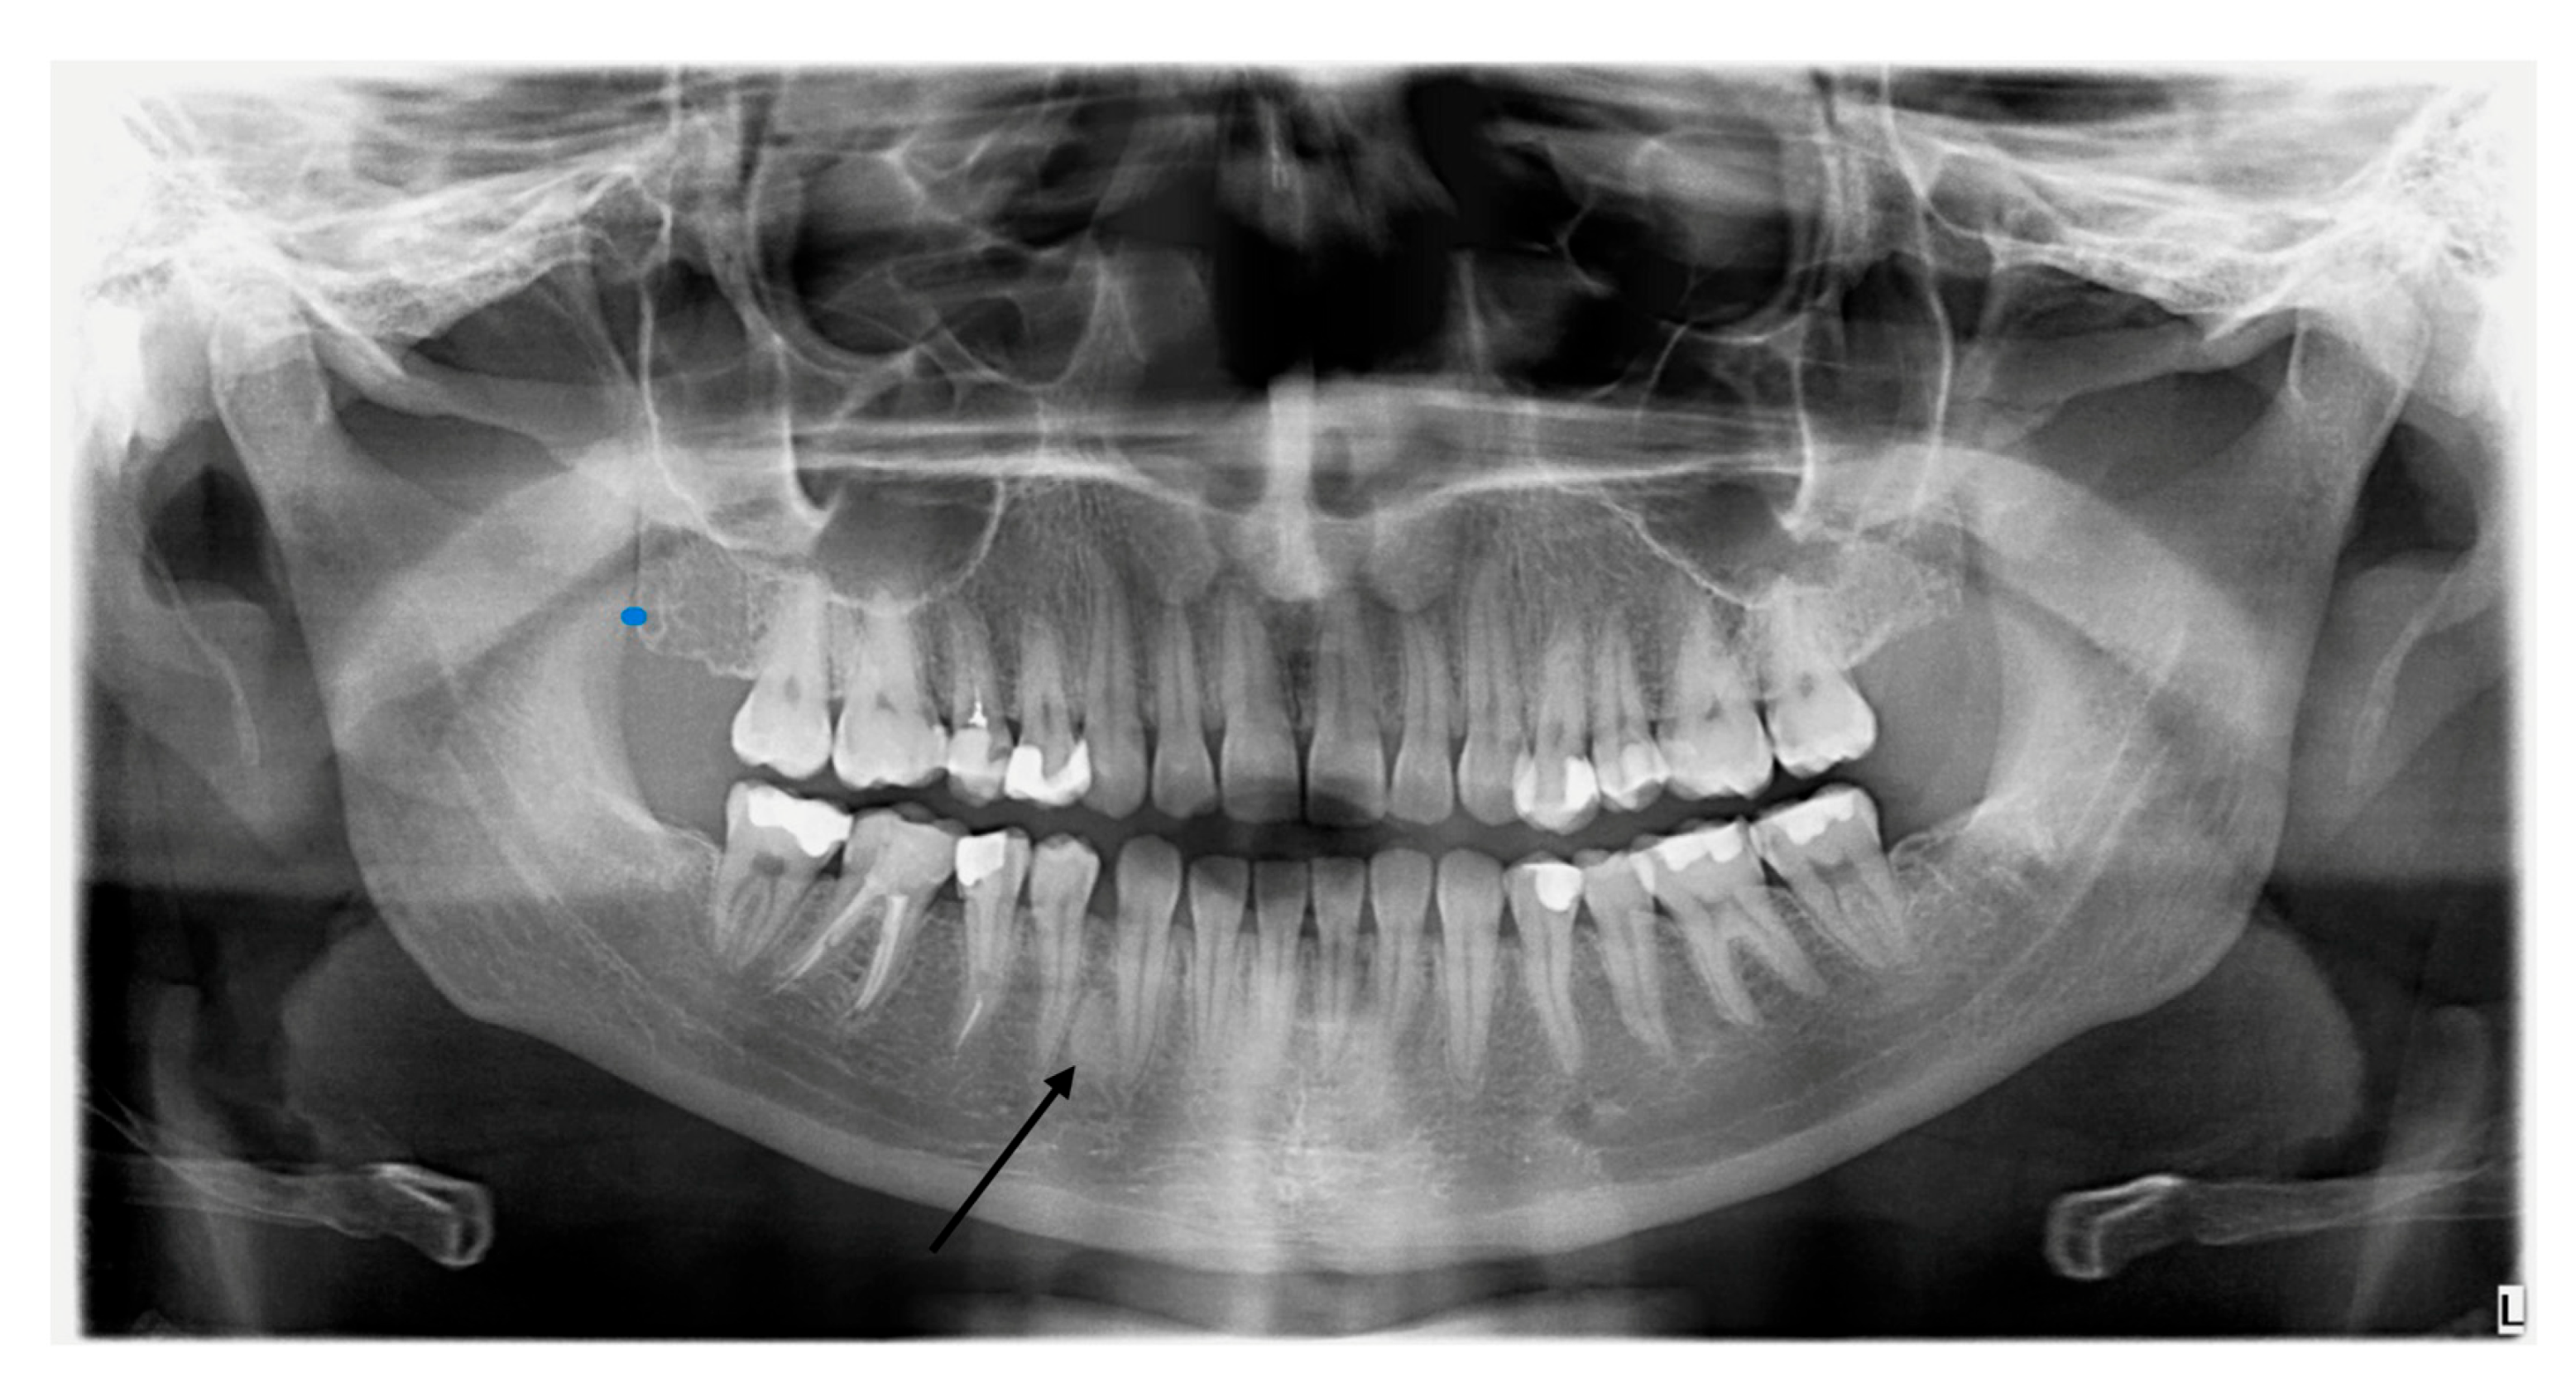

2.4. Dental Examination